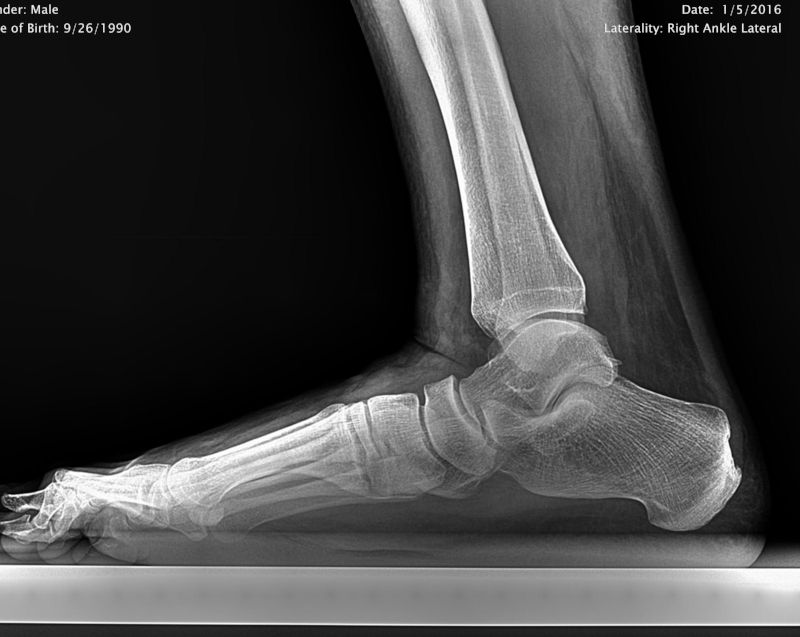

Flat Foot